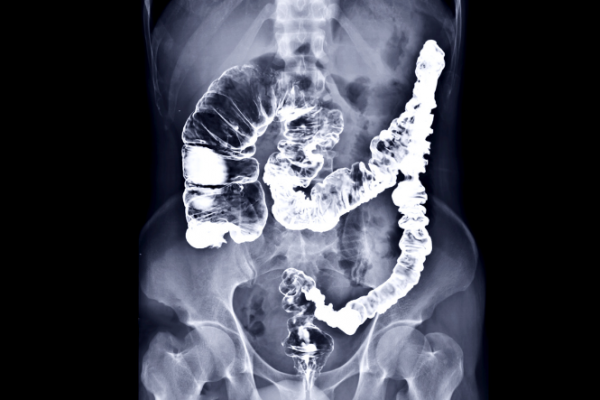

These lower parts of your bowel aren't easy to see on an X-ray. Barium coats the inside lining of your bowel to make it easier to see changes such as tumours, polyps, blockages, pouches and narrowed parts. Barium isn't radioactive and isn't absorbed by your body. It's passed out with your poo. The image below shows the highlighted area on an X-ray.

X-ray image of colon after barium enema

Image credit: Canva